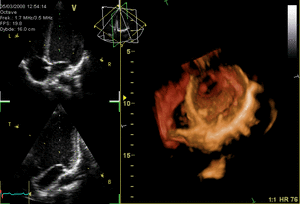

When valves don't work well, a person might feel tired, short of breath, or have swelling. Doctors can find out if there's a valve problem using a special type of ultrasound called an echocardiography. This uses sound waves to create pictures of the heart and its valves.